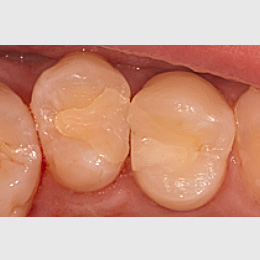

Fallbeispiel: Zahn 15 mit starker Krümmung

Jeder Zahn ist einzigartig – in diesem Fall zeigte sich Zahn 15 mit einer starke Wurzelkrümmung. Trotz der starken Krümmung konnte eine Wurzelkanalbehandlung durchgeführt werden und somit auch die Brücke erhalten werden.